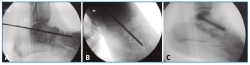

Figura 3. Reducción y fijación con aguja guía de la articulación astrágalo-escafoidea bajo control fluoroscópico en lateral (A) y anteroposterior (B) y osteosíntesis a compresión con un tornillo (C; ICOS® 6,5 mm).

Figura 4. Fijación con aguja guía de la articulación subastragalina bajo control fluoroscópico en lateral (A) y anteroposterior (B) y osteosíntesis a compresión con un tornillo (C; ICOS® 6,5 mm).

Finalmente, se realiza la osteosíntesis a compresión con un tornillo (ICOS® 6,5 mm; un caso con tornillo HCS® Synthes 6,5) primero de la TN (Figura 3) y después de la ST (Figura 4)(29)(30).